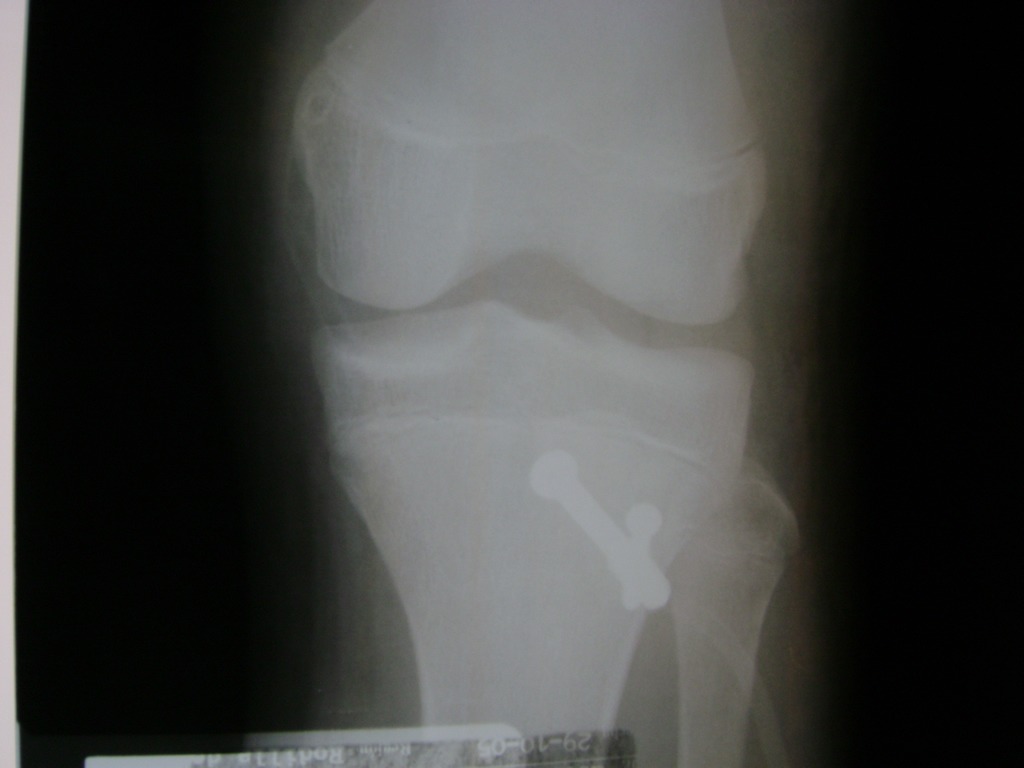

Cirugías de Codo - Rodilla

La artroscopia de rodilla es un cirugía en el cual la estructura interna de la articulación es examinada ya sea para realizar un diagnostico o para realizar un tratamiento, este procedimiento se realiza utilizando un instrumento parecido a un pequeño tubo llamado artroscopio.